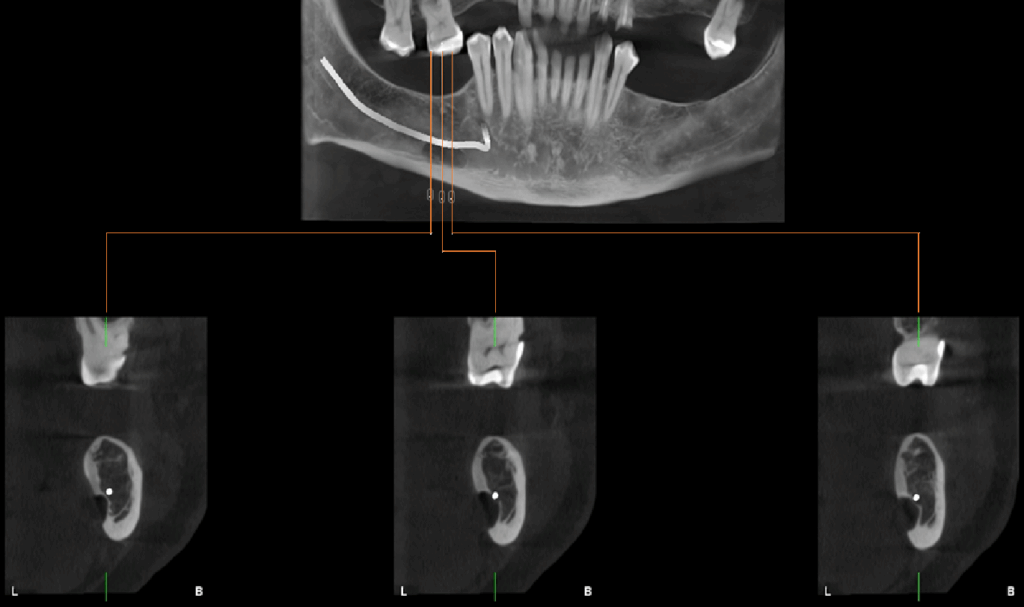

A la evaluación de la tomografía computarizada de campo mediano se observa en cortes axiales la misma imagen efectivamente parcialmente corticalizada, y que ocasiona la perdida de continuidad sólo de la tabal ósea lingual, a pesar de que en los cortes tangenciales de vestibular a lingual se asemejaría a la forma de una lesión quística en formación que se encuentra en contacto con el reborde basal, también notamos que respeta la cortical del conducto dentario inferior, finalmente en los cortes transaxiales y en la reconstrucción 3D podemos tener una mejor visión de la cavidad que no posee características patologícas y las estructuras óseas y dentarias adyacentes que no presentan alteración aparente.

CORTES TRANSAXIALES

Conclusión: defecto óseo de Stafne.